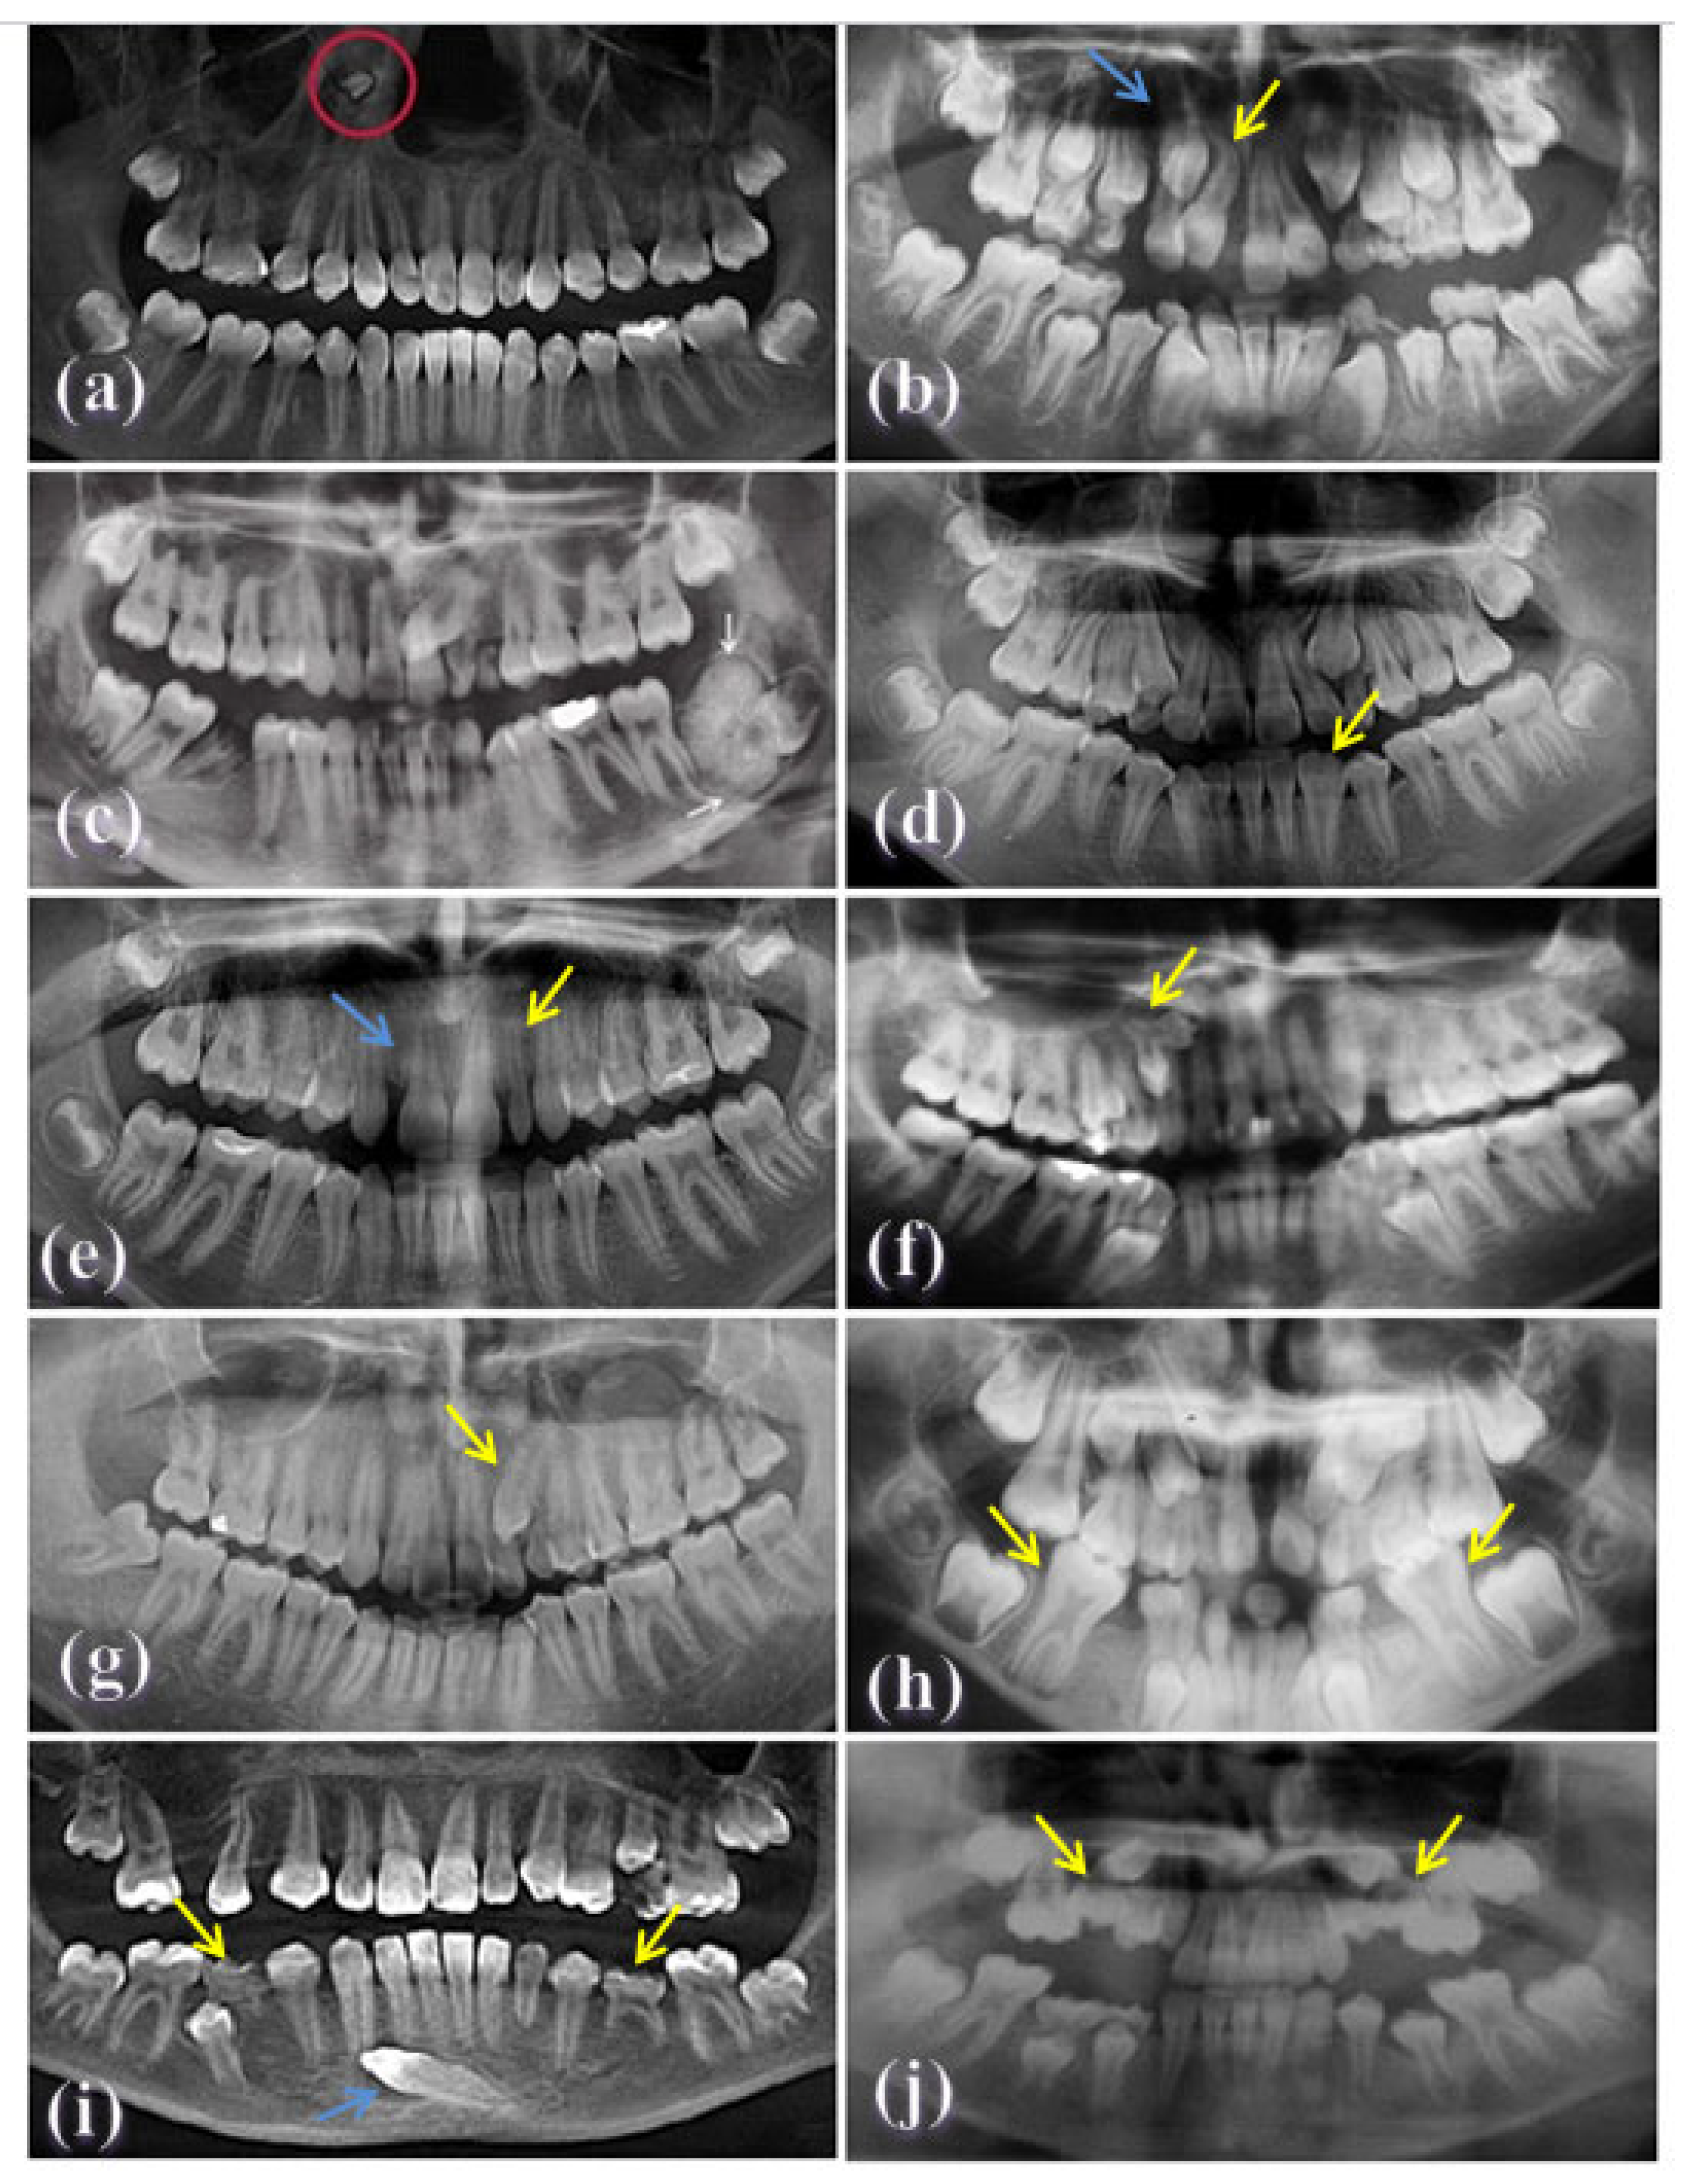

| Dental Anomaly | Diagnostic Criteria |

|---|---|

| Missing teeth | Lack of development of one or more permanent teeth. |

| Supernumerary teeth | An excess in the normal number of permanent teeth due to the development of additional teeth. |

| Peg-shaped teeth | A tooth with an incisor mesio-distal width smaller than its cervical width [33]. |

| Fusion | Union between two separate tooth buds during dental development involving the crowns and/or the roots [34]. |

| Gemination | Inadequate division of a tooth germ, resulting in the formation of two partially or completely separated crowns with one root and one root canal. It is clinically characterized by incisal notching on an enlarged crown [34]. |

| Transposition | Interchange in the position of two adjacent permanent teeth in the same quadrant of the dental arch [35]. |

| Transmigration | Movement of an impacted tooth across the jaw midline [36]. |

| Ectopic | An erupted tooth that is not in its proper position in the dental arch (e.g., the tooth is located mesially/distally or vestibularlly/orally outside the dental arch [37]. |

| Impaction | Interruption in the eruption of a tooth caused by a clinically or radiographically detectable physical barrier in the eruption path, or because of an abnormal position of the tooth [38,39]. |

| Submerged | A deciduous erupted tooth that failed to reach the occlusal level of the fully erupted adjacent teeth by at least 2 mm. |

| Retained | Failure of the primary tooth to exfoliate at the proper developmental stage (more than one year late to erupt from its permanent successor) [39]. |

| Dilacerations | Teeth with bends or changes in the long axis of their crowns, crown-roots, or roots. This is usually following trauma to the developing tooth bud. |

| Taurodontism | The furcation areas on the molar teeth are located more epically than normal, and the pulp chamber appears elongated as a result. This anomaly is detected in radiographs and is seen in both dentitions, but is morecommon in the permanent dentition [2]. |

| Odontoma | An odontoma is a tumor-like malformation that contains elemental tooth matrix materials [40]. |